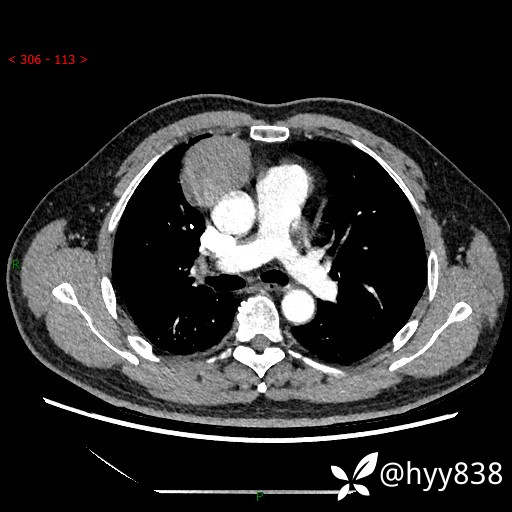

动脉期+静脉期

各期CT值